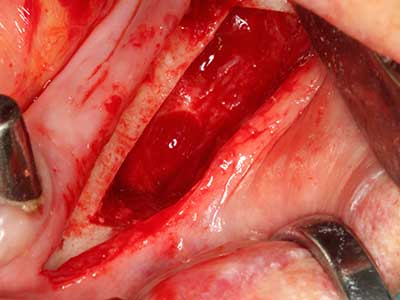

Indikation: Nervnahe Präparation

Wie bereits erwähnt lassen sich auch im Bereich der chirurgischen Zahnerhaltung Indikationsgebiete für die Piezochirurgie finden. Durch die Verwendung von speziellen Arbeitsspitzen wird die Darstellung der Wurzelspitze erleichtert, und gerade im unteren Prämolaren- und oberen Seitenzahnbereich lassen sich Nerven und Kieferhöhlenschleimhäute einfacher schützen. Bei undichtem apikalen Abschluss präparieren abgewinkelte Diamantspitzen zielgenau die Resektionskavität für das retrograde Wurzelfüllmaterial. Die Spitzen können durch die Ultraschalltechnik sehr grazil gestaltet sein, was Übersicht und Größe der Zugangskavität verbessert. So gehört in dieser Indikation die Anwendung der Ultraschallchirurgie zu den Standardverfahren der Wurzelspitzensresektion (Del Fabbro, Tsesis et al. 2010, Scarano, Artese et al. 2012).

Indikation: Wurzelspitzenresektion